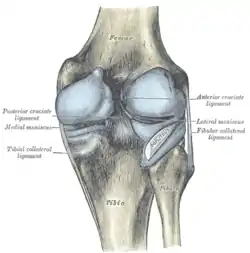

The ligaments surrounding the knee joint offer stability by limiting movements and, together with the menisci and several bursae, protect the articular capsule.[16]

Intracapsular

The knee is stabilized by a pair of cruciate ligaments. These ligaments are both extrasynovial, intracapsular ligaments.[17] The anterior cruciate ligament (ACL) stretches from the lateral condyle of femur to the anterior intercondylar area.[13] The ACL is critically important because it prevents the tibia from being pushed too far anterior relative to the femur.[13] It is often torn during twisting or bending of the knee.[18] The posterior cruciate ligament (PCL) stretches from medial condyle of femur to the posterior intercondylar area. This ligament prevents posterior displacement of the tibia relative to the femur.[13] Injury to this ligament is uncommon but can occur as a direct result of forced trauma to the ligament.

The transverse ligament stretches from the lateral meniscus to the medial meniscus. It passes in front of the menisci. It is divided into several strips in 10% of cases.[10]:208 The two menisci are attached to each other anteriorly by the ligament.[19] The posterior (of Wrisberg) and anterior meniscofemoral ligaments (of Humphrey) stretch from the posterior horn of the lateral meniscus to the medial femoral condyle. They pass anterior and posterior to the posterior cruciate ligament respectively.[13][10]:208 The meniscotibial ligaments (or "coronary") stretches from inferior edges of the menisci to the periphery of the tibial plateaus.

Extracapsular

The patellar ligament connects the patella to the tuberosity of the tibia. It is also occasionally called the patellar tendon because there is no definite separation between the quadriceps tendon (which surrounds the patella) and the area connecting the patella to the tibia. [20] This very strong ligament helps give the patella its mechanical leverage [21] and also functions as a cap for the condyles of the femur. Laterally and medially to the patellar ligament the lateral and medial retinacula connect fibers from the vasti lateralis and medialis muscles to the tibia. Some fibers from the iliotibial tract radiate into the lateral retinaculum and the medial retinaculum receives some transverse fibers arising on the medial femoral epicondyle.[10]:206

The medial collateral ligament (MCL a.k.a. "tibial") stretches from the medial epicondyle of the femur to the medial tibial condyle. It is composed of three groups of fibers, one stretching between the two bones, and two fused with the medial meniscus. The MCL is partly covered by the pes anserinus and the tendon of the semimembranosus passes under it.[10]:206 It protects the medial side of the knee from being bent open by a stress applied to the lateral side of the knee (a valgus force).[10]:206

The lateral collateral ligament (LCL a.k.a. "fibular") stretches from the lateral epicondyle of the femur to the head of fibula. It is separate from both the joint capsule and the lateral meniscus.[10]:206 It protects the lateral side from an inside bending force (a varus force). The anterolateral ligament (ALL) is situated in front of the LCL.